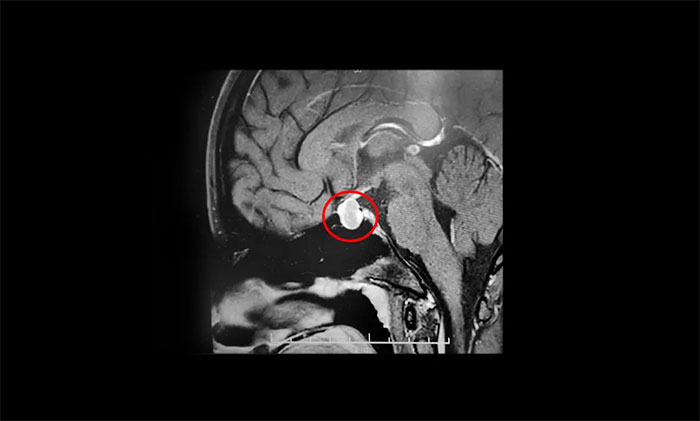

鞍区MRI显示:蝶鞍稍扩大,鞍底骨质下陷。鞍内垂体上缘稍膨隆,腺垂体中央见一枚类椭圆形异常信号,大小约1.6×1.2×0.9cm。

T1WI上呈高信号、T2WI呈低信号,轮廓光整,静脉团注Gd-DTPA后多个时相动态增强。冠状位T1WI见早期病变强化不明显,与明显强化垂体对比明显,病变相对于正常腺体呈低信号,境界变清晰。

垂体柄缩短,未见偏移;视交叉轻度上抬;双侧海绵窦未见异常改变;所示蝶窦局部黏膜增厚。